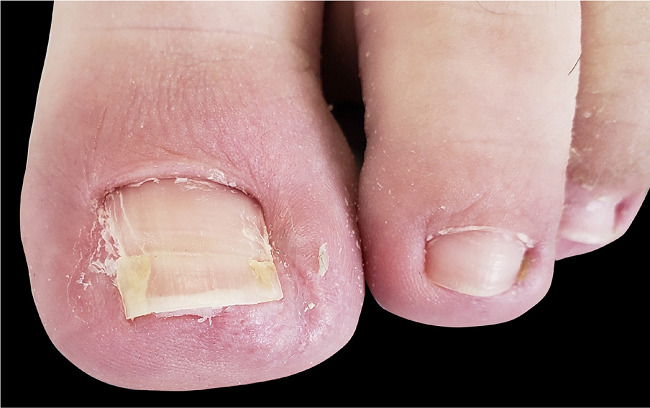

Devido ao diagnóstico de onicocriptose nas duas dobras ungueais laterais e à formação de unha em arpão em uma delas, o paciente foi encaminhado para cirurgia. Realizamos a ressecção do excesso de tecido das dobras laterais, o que permitiu a visualização da espícula pontiaguda na porção lateral da lâmina ungueal (Figura 2); seguimos com a avulsão de uma faixa lateral da unha e finalizamos com a cauterização química (fenol 88%) do segmento lateral da matriz e da porção cruenta das dobras laterais (Figura 3). A cicatrização ocorreu por segunda intenção.

O paciente evoluiu bem no pós-operatório, sem sinais de recidiva e com bom resultado estético após seis meses de evolução (Figura 4).